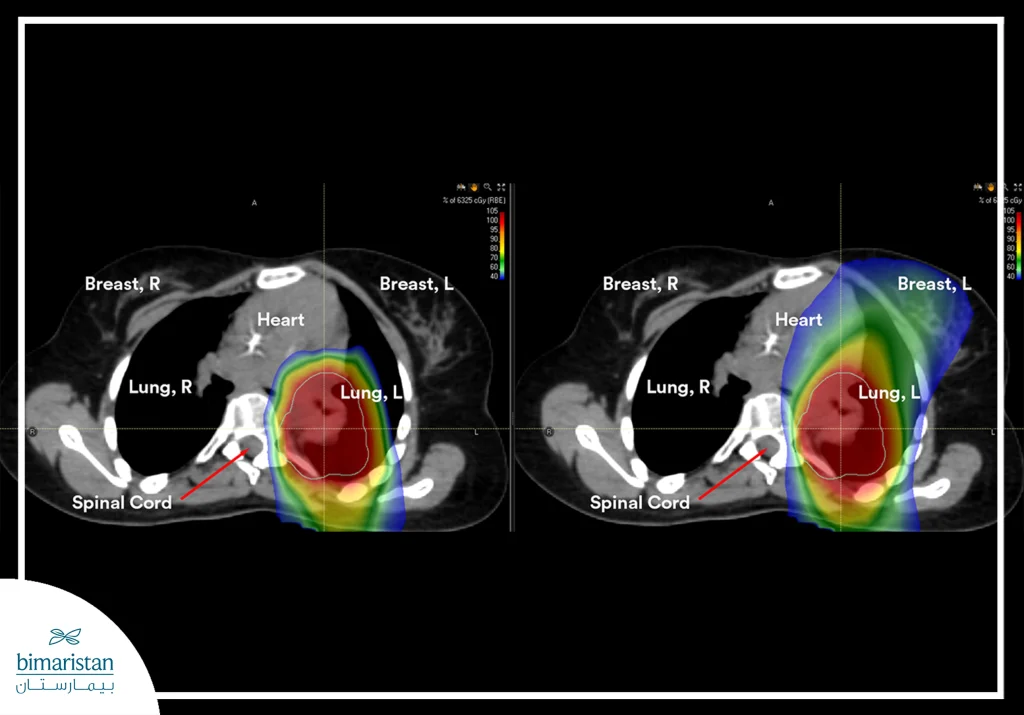

Proton therapy for lung cancer relies on directing a highly precise beam of protons toward the tumor, allowing most of the radiation energy to be deposited within the cancer cells themselves. This precise targeting helps shrink the tumor or destroy malignant cells while preserving the surrounding healthy tissues, an essential advantage given the proximity of lung tumors to vital organs within the chest.

This level of precision enables clinicians to deliver high radiation doses directly to the tumor while reducing exposure of healthy tissues. Specialized techniques are also employed to limit the impact of respiratory motion during treatment, helping improve targeting accuracy and reduce radiation exposure to the heart, the opposite lung, and other structures within the chest.

Proton therapy for lung cancer enables the delivery of high‑dose radiation precisely to the tumor while reducing exposure to surrounding healthy tissues, an important advantage given the proximity of lung tumors to critical structures in the chest. Its key benefits include:

- Minimize radiation exposure to healthy lungs, heart, esophagus, and spinal cord